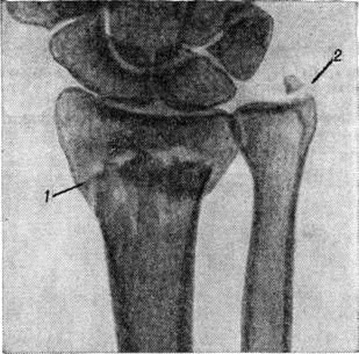

Основной рентгенологическое признак нарушения целости кости — линия Переломы Большое диагностическое значение имеет смещение отломков, наличие которого настолько бесспорно доказывает нарушение целости кости, что надобность в дифференциальной диагностике отпадает. Как бы подробно ни была описана рентгенологическое картина Переломы, наиболее полное и правильное представление о степени и характере смещения отломков врач может составить лишь при непосредственном просмотре снимков. Захождение отломков одного за другим при продольном смещении на рентгенограмме в одной проекции может сопровождаться наслоением теней концов отломков — так называемый суперпозицией теней. В этом случае точное определение смещения отломка возможно на основании данных снимков во второй проекции. При Переломы плоских костей (лопатка, ребра, таз и другие), при которых по техническим причинам производство снимка во второй проекции затруднено, суперпозиция отломков часто является единственным достоверным признаком Переломы Распознавание продольных смещений с расхождением отломков обычно не представляет каких либо затруднений. Подобного рода смещения наблюдаются при Переломы надколенника с разрывом связочного аппарата, локтевого отростка, вертелов бедра, отрывах костных выступов, к которым прикрепляются мышцы, сокращающиеся при повреждениях и приводящие к расхождению. Интерпозиция мягких тканей между отломками костей при рентгенологическое исследовании не распознается. Различные виды Переломы в наиболее информативных проекциях представлены на рисунок 4—11.

Рис. 6.

Прямая рентгенограмма лучезапястного сустава: перелом (I) дистального метаэпифиза лучевой кости и отрыв шиловидного отростка (2) локтевой кости.